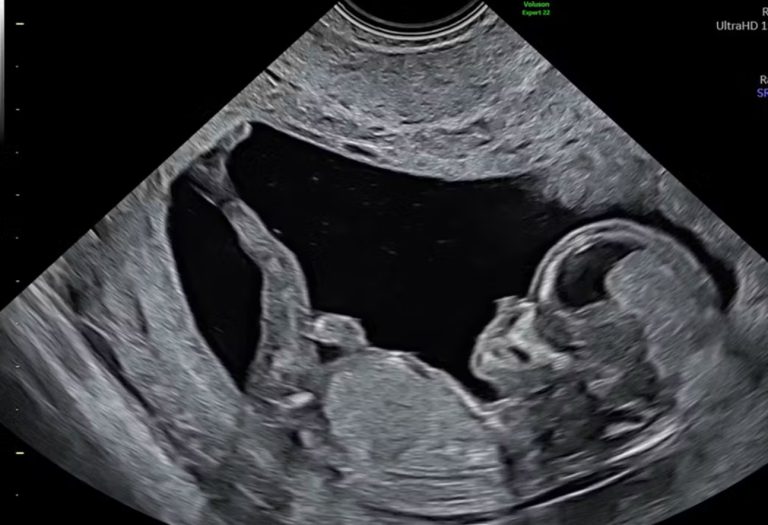

Echografie en andere beeldvormingstechnieken zorgen voor een sterkere emotionele betrokkenheid van ouders bij hun ongeboren baby. Dit geldt voor zowel moeders als vaders. Het zien van de beelden helpt ouders om zich meer verbonden te voelen en het bevordert de ontwikkeling van een hechte ouder-kind relatie, zo blijkt uit literatuuronderzoek gepubliceerd in het Journal of Reproductive and Infant Psychology.

De onderzoekers analyseerden 23 Engelstalige studies die vanaf 2000 zijn gepubliceerd. Veel ouders geven aan dat ze de eerste echo van hun baby ervaren als een mijlpaal in de zwangerschap. Na het bekijken van de beelden vinden ouders het makkelijker om hun ongeboren kind voor zich te zien en dit versterkt gevoelens van liefde en verantwoordelijkheid.

Moderne technieken zoals 3D- of 4D-echo’s leiden niet per se tot meer emotionele betrokkenheid. Volgens de onderzoekers is het niet de technologie die de band versterkt, maar de wijze waarop de zorgverlener de beelden duidt.